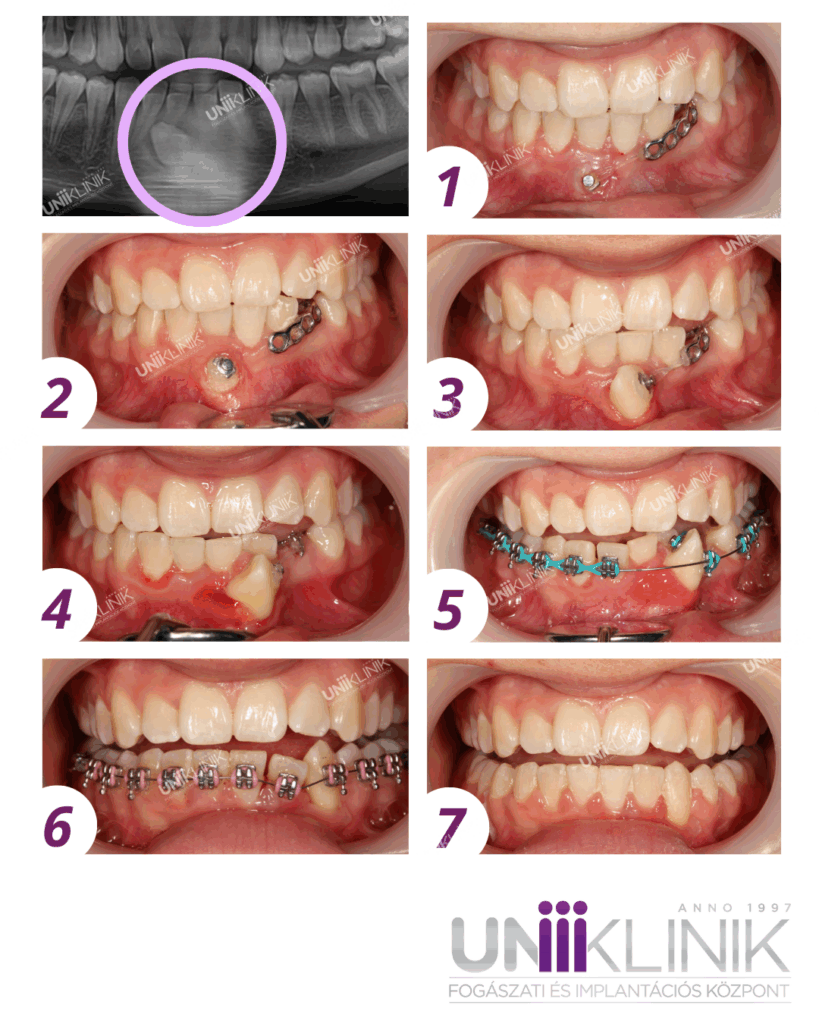

Ektópiás Szemfog Fogszabályozása